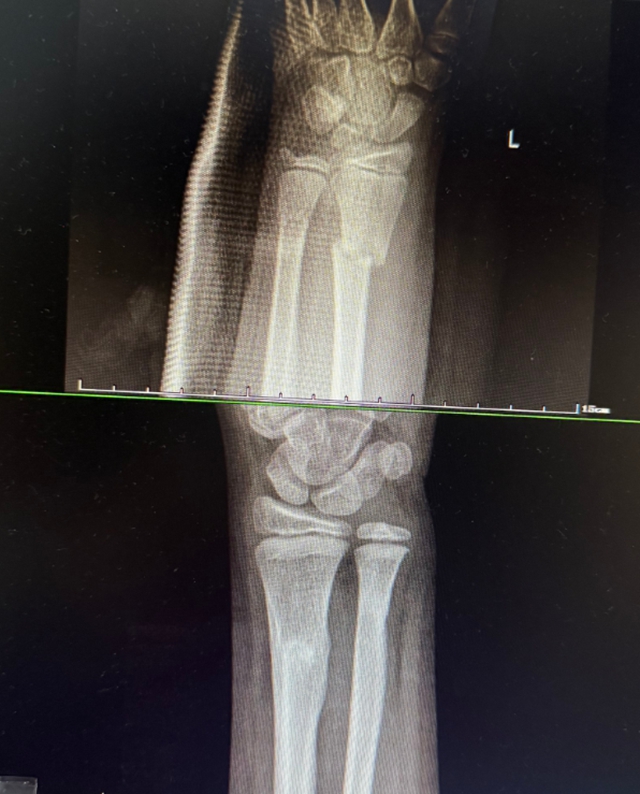

西安9岁女孩小璐(化名)玩耍时意外摔倒,导致左手前臂扭曲。紧急送医后,X光片显示其尺桡骨双骨折,断端已移位。父母带她辗转当地多家医院,均建议手术复位。

次日,一家人从西安来到医院正骨病房。此时付至江主治中医师刚结束治疗,便立刻接过病历和片子。细细比对后,他轻触小璐前臂检查,动作轻柔:“孩子骨骼柔韧,尺桡骨双骨折,首选中医正骨保守治疗……”这句话让小璐妈妈喜极而泣。

康复归来,三月余重绽舞姿